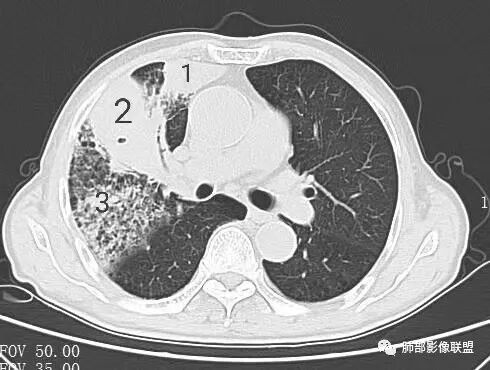

病灶1、2、3,怎么用鳞癌、腺癌解释?

这能用缺血性坏死解释吗?

肉芽肿性炎,支气管肺炎,坏死性炎,

上肺优势;3是血管侵袭

奴卡>放线菌

2呈现奴卡之角

这个病灶,鳞癌肯定可以排除了

腺癌、放线菌也不符合,奴卡解释可以